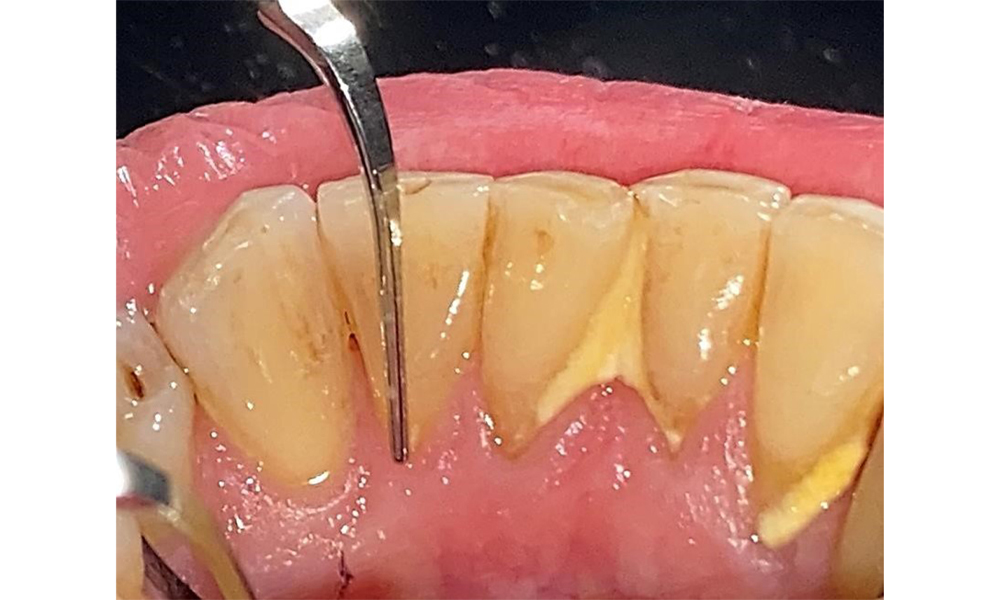

Der Patient hat ein vollbezahntes Gebiss mit 28 Zähnen, an welchen sich im Molaren- und Prämolarenbereich Amalgamfüllungen und Compositefüllungen befinden. An Zahn 14 zeigt sich ein sichtbarer klinischer Randspalt. Zahn 27 hat ein suffizientes Goldinlay. Zudem zeigen sich generalisierte Attritionen und Abrasionen. (Abb. 2, Abb. 3, Abb. 4, Abb. 5, Abb. 6)

Der Patient hat eine Parodontitis Stadium II, Grad B (5). Die klinischen Sondierungstiefen liegen mit 1-3mm im physiologischen Bereich. Lokalisierte Sondierungstiefen finden sich an 17 und 27 jeweils mesiopalatinal mit 5mm. Es liegen generalisierte Rezessionen von 1-3mm vor mit partiellem Verlust der Interdentalpapillen (Abb. 2, Abb. 3, Abb. 4)

Der Patient ist ein gut eingestellter Diabetiker. Somit ergibt sich aus der Anamnese kein erhöhtes Komplikationsrisiko für die Behandlung. Grundsätzlich ist vor jeder Behandlung der HbA1c-Wert abzufragen. Die Befundaufnahme intraoral ist entscheidend für den Bedarf an dentaler und parodontaler Therapie. Aufgrund der Parodontitis ist ein parodontaler Befund mit Taschentiefensondierung und Blutungsstatus in jeder Sitzung unerlässlich (Abb. 8). Dieser gibt den individuellen Therapiebedarf vor und es kann auf eine mögliche Progression der parodontalen Vorerkrankung reagiert werden.

In der Instrumentierung sind bezüglich der Methodenwahl keine Einschränkungen gegeben. Aufgrund der parodontalen Vorerkrankung und dem hohen Rezidivrisikos ist die Vorbeugung einer Erkrankungsprogression durch die regelmäßige supra- und subgingivale Instrumentierung unerlässlich. Die Wahl der Instrumente zur mechanischen Biofilmentfernung ist aus allgemeingesundheitlicher Sicht nicht eingeschränkt und erfolgt bedarfsgerecht. Harte und mineralisierte Beläge wie Zahnstein und Konkremente sind mittels Handinstrumenten oder Schall/ Ultraschallscalern zu entfernen (Abb. 9) (8, 9).